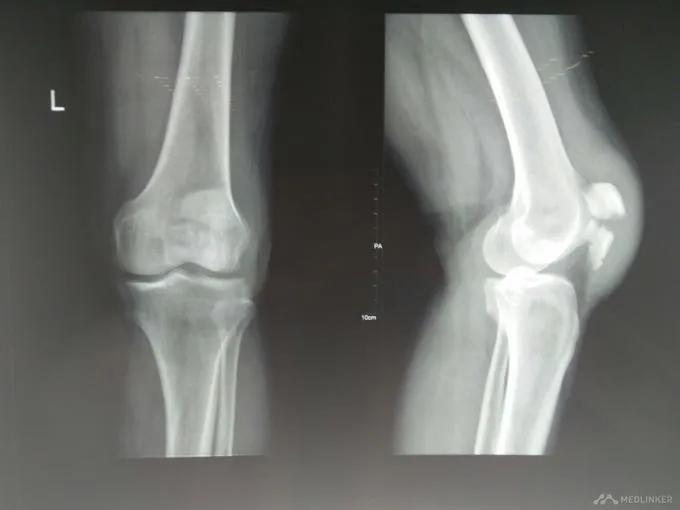

下面是我前两天做的一台髌骨骨折手术,患者男性,34岁,因送外卖骑电动车摔倒致左膝着地,急诊拍片示左髌骨骨折。

术前左膝关节X线正侧位片